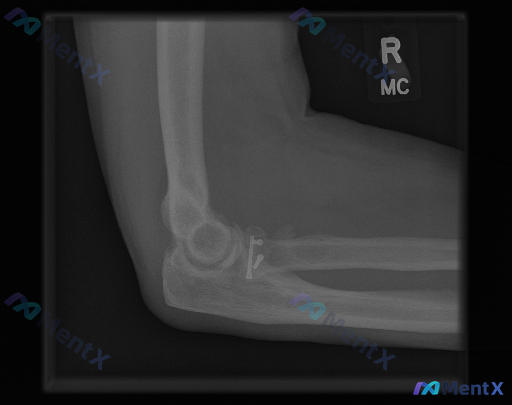

整理到一张右侧肘关节的术后X光片资料,先和大家同步一下明确的影像表现: 1. 右侧桡骨头/颈部区域可见金属内固定(接骨板+螺钉),位置看着基本稳定,没有明显断裂或移位 2. 该区域原骨折线模糊,骨小梁有重建,符合愈合期或已愈合的改变 3. 肘关节对位还行,关节间隙没有明显狭窄,也没看到明显游离体 4...